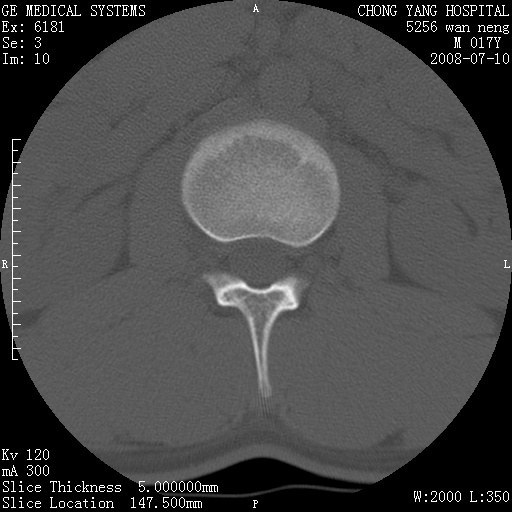

腰3、4椎弓崩裂

腰3、4椎弓不连

支持:腰3、4椎弓峡部崩裂。

腰3、4椎弓峡部不连

支持:腰3、4椎弓峡部崩解。

腰3、4,如受过外伤则为陈旧骨折,否则为骨质不连

图片漂亮,目前也只能看到腰3、4骨质不连

腰3、4椎弓峡部裂。

腰3、4椎弓峡部裂。支持

重建图像见多个椎弓峡部不连(不足为据),平扫未见异常。

支持腰3、4椎弓峡部崩裂。